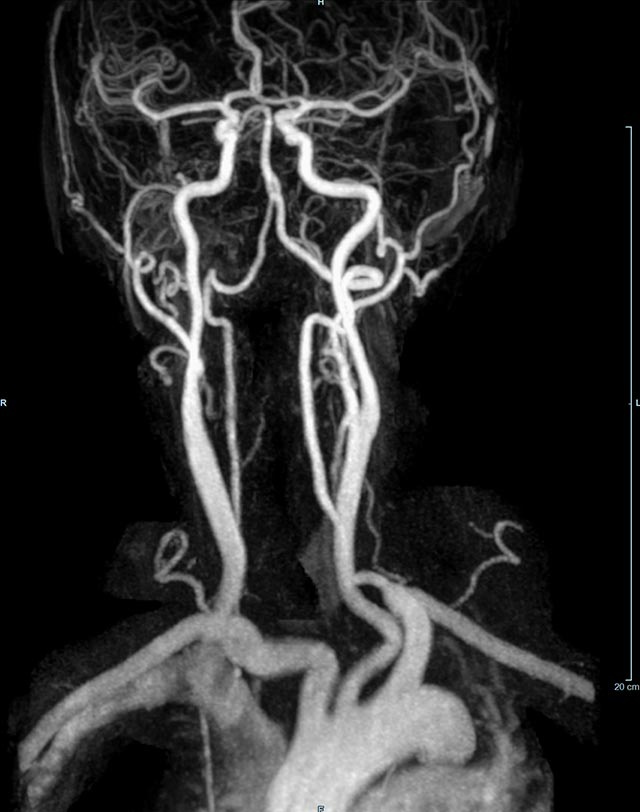

- MR-Angiografie ohne Kontrastmittel

- Time of Flight (TOF)-Angiographie

- Phasenkontrastangiographie (PCA). Geeignet zur Quantifizierung Stenose-/Insuffizienzgrad z.B. bei Herzklappen, falls echokardiographisch die Untersuchungsbedingungen eingeschränkt sind.

Je nach Fragestellung und Körperregion Gefäßdarstellung ohne Kontrastmittel bei Kontrastmittelunverträglichkeit oder terminaler Niereninsuffizienz möglich.

- MR-Angiographie mit Kontrastmittel

- Erfassung arterieller und venöser Gefäße/Bypässe aller Körperregionen mit 3D-Rekonstruktion

- je nach klinischer Fragestellung zeitaufgelöste MR-Angiographie (4D-MRA) z.B. bei Frage arteriovenöse Fistel/ Shunt oder Darstellung Unterschenkelarterien vor geplanter Bypassoperation.

Durchführung dieser Untersuchung nur an den Standorten am Diakonissenkrankenhaus und am Markkleeberg-Center